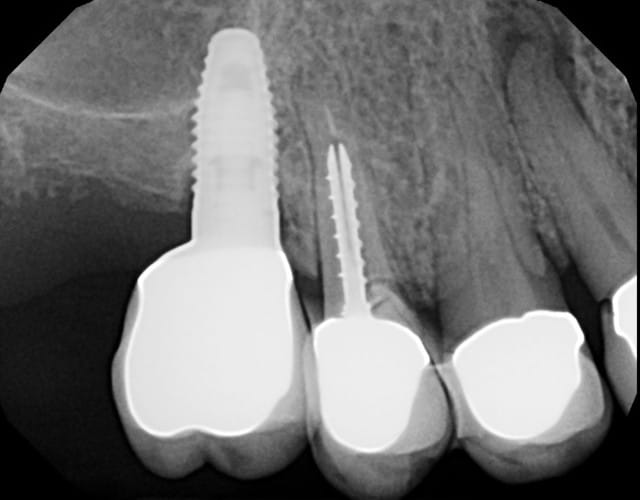

Patiente adressée pour évaluation :

son dentiste ne sait que faire.

À l'examen :

13 : belle fistule vestibulaire, mobilité, carie cervicale

14 : mobilité +++

15 : fracture racine (?), carie cervicale

Les implants datent de 5-6 ans (par un autre CD, la patiente a depuis déménagée).

Le bas , pas touche cette année, on verra en 2012.

Votre plan de tx ?